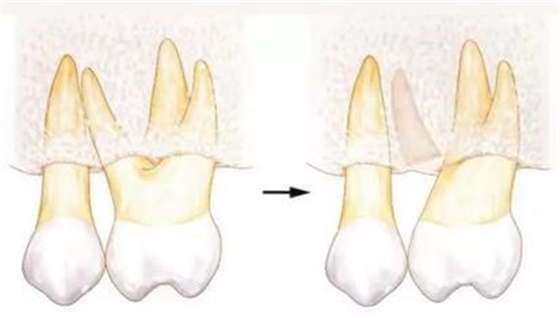

[針對(duì)牙根接近的牙周外科處理--牙體成形]

牙根一般根尖側(cè)較細(xì),所以牙根接近會(huì)使根尖部分減少。進(jìn)行牙周外科處理時(shí),如果能夠?qū)⒐墙M織切除一部分的話,就能通過(guò)骨組織切除和牙體成形來(lái)解決牙根接近的問(wèn)題。

▲圖6

如果可以在一定程度上削除骨組織的話,就可以通過(guò)牙體成形和骨外科處理來(lái)獲得biologic width,并可以解決牙根接近的問(wèn)題。